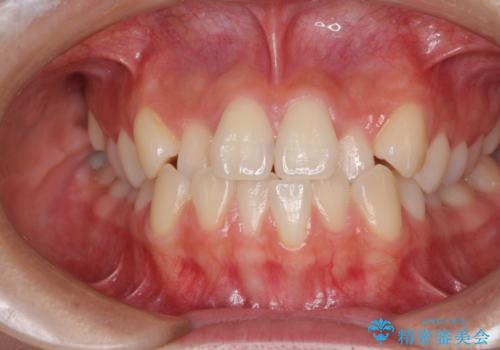

前歯の反対咬合をワイヤー矯正で改善して噛みやすく